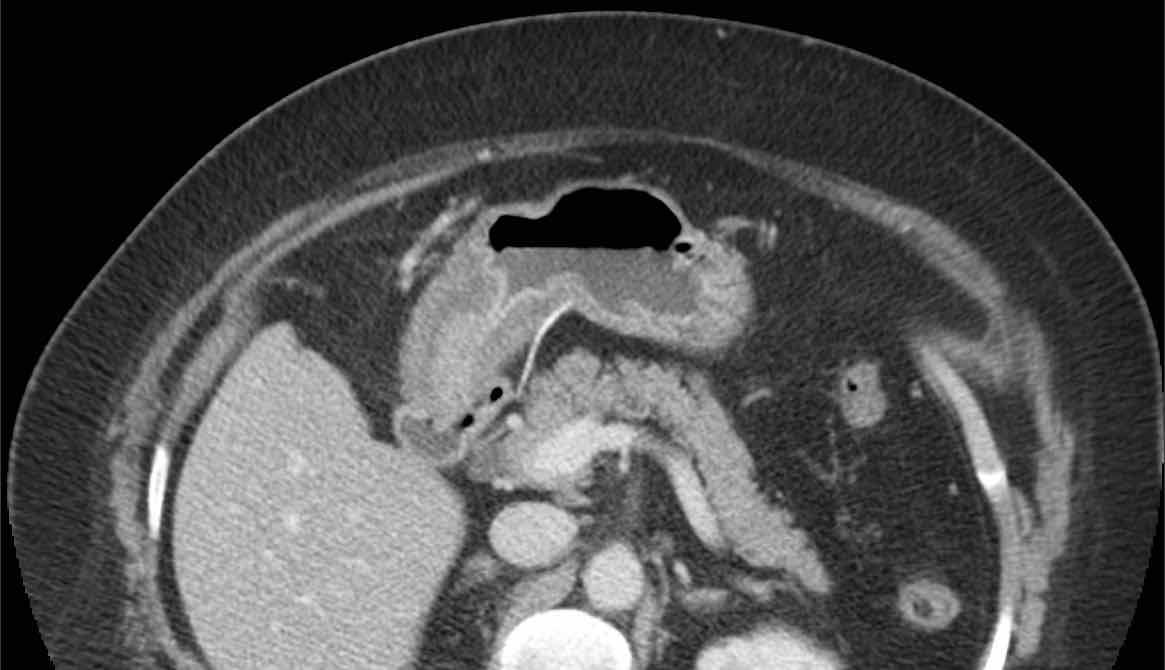

Bệnh nhân nữ 59 tuổi với cơn đau thượng vị không điển hình kéo dài hai ngày.

Siêu âm phát hiện dày thành đáng kể vùng hang vị trước môn vị, trong đó có cấu trúc tăng âm, dạng cong (đầu mũi tên), nghi ngờ xương cá.

CT xác nhận chẩn đoán.

Lưu ý rằng xương cá (mũi tên) có thể dễ dàng bị bỏ sót nếu chỉ xem trên mặt phẳng cắt coronal của CT.

Bệnh nhân hồi phục tốt sau khi lấy dị vật qua nội soi.

Siêu âm và CT cho thấy xương cá xuyên thủng thành dạ dày ngay trước môn vị.

Khi nội soi dạ dày không tìm thấy xương cá, mà chỉ thấy phù nề niêm mạc cục bộ với loét trung tâm (mũi tên).

Việc đưa sâu dụng cụ kẹp lớn vào vùng này cuối cùng đã thành công trong việc gắp được xương cá.